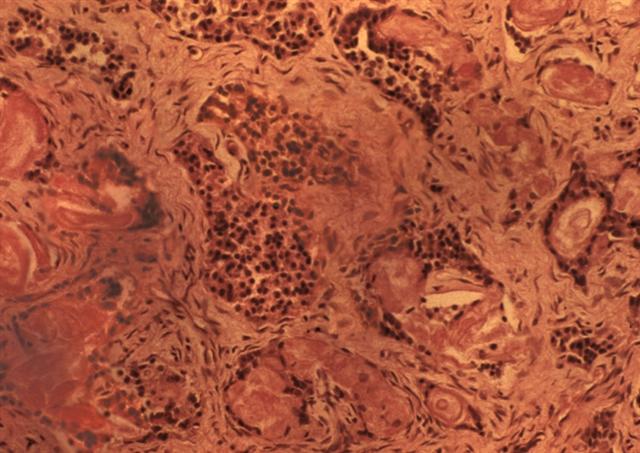

Рис. 1. Микропрепарат поджелудочной железы при смешанной форме муковисцидоза: 1 — расширенные и заполненные ацидофильным слоистым секретом междольковые и внутридольковые протоки; 2 — разрастания соединительной ткани. Окраска гематоксилином и эозином; ´80.